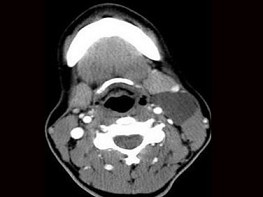

6.CT檢查結果見下圖,本患者應考慮為  (    )